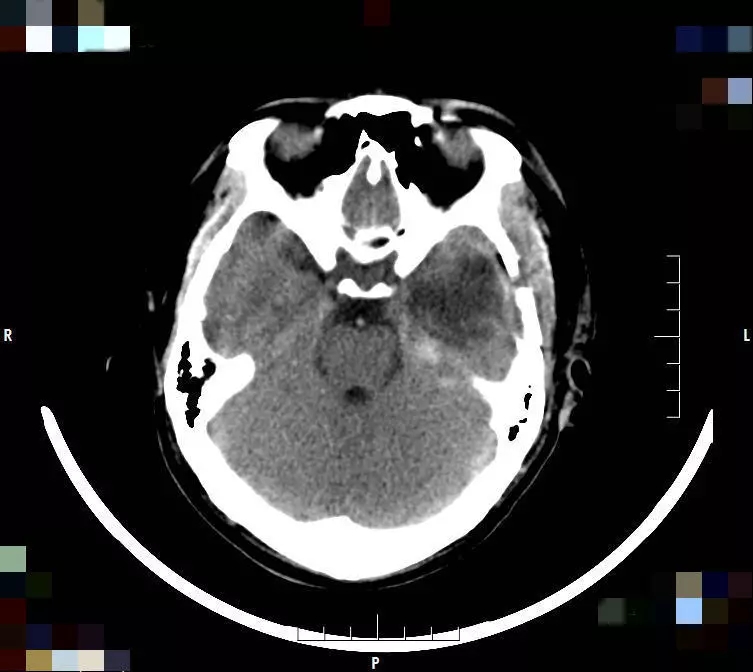

▲ 术前

▲ 术后

患者入院后,武跃辉主治医师详细了解患者病情后,为其做了详细的神经电生理学、影像学等检查,单峤、李培栋、吴艳芝三位专家结合患者的病史、癫痫发作形式、治疗经过以及辅助检查结果,为其制定了个体化的治疗方案。该方案认为患者为局灶性癫痫发作,有明确的癫痫病灶,有望通过术前精准定位、术中电生理检测、手术切除的方式使患者达到治愈。

确定该治疗方案后由单峤主任医师主刀,李培栋主任医师、武跃辉主治医师及高东海医师协助下为患者实施了手术,术后患者恢复良好,至今未再出现癫痫发作。单峤主任团队通过精湛的医术再次拯救了一个家庭,获得了患者及家属的高度赞扬。